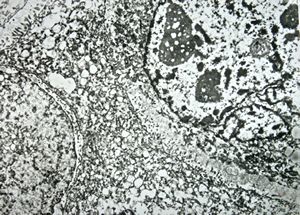

M,50y. | Pneumocystis carinii - lung